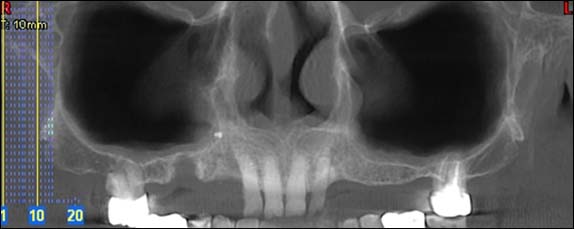

Panoramique

Cette radio permet d’appréhender l’ensemble de votre dentition et des structures adjacentes.

Reconstruction panoramique